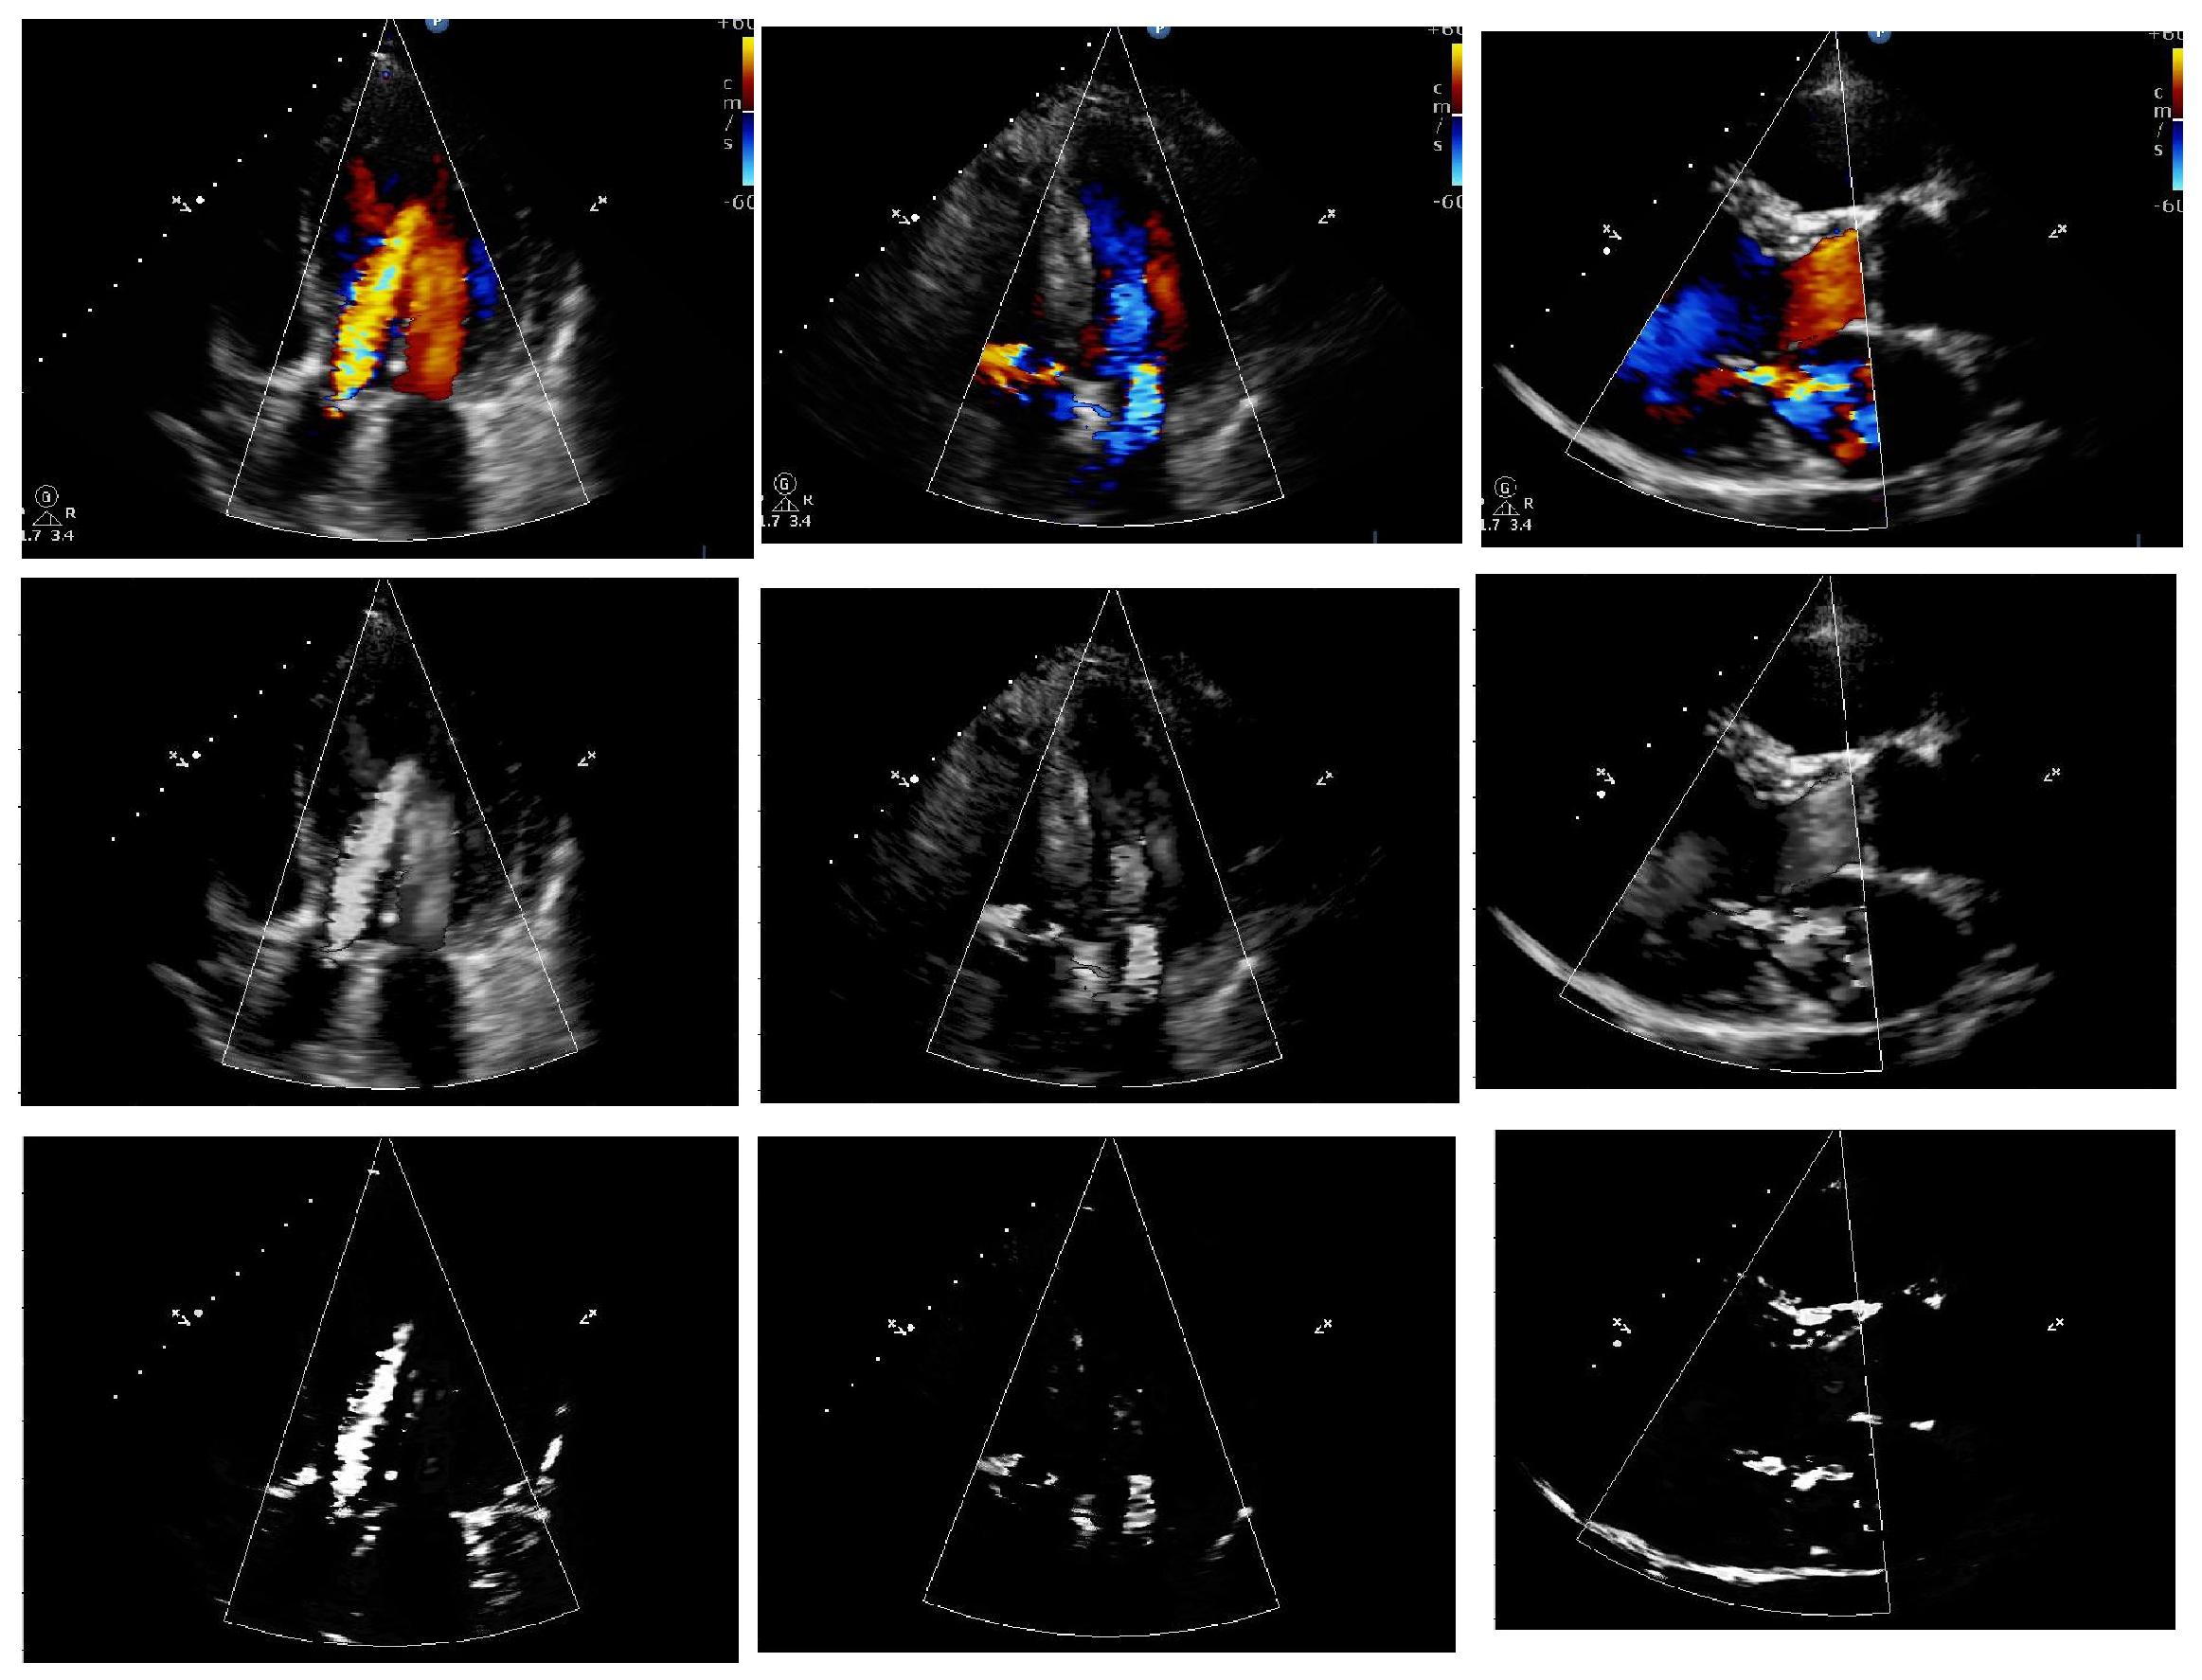

4.3.1. Preprocessing and Segmentation Output